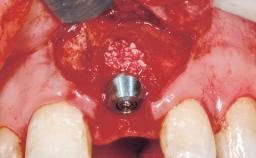

Late Flapless Placement of an Implant in a Maxillary Left Central Incisor Site

A 39-year-old male patient presented with a chief complaint of discomfort and gingival discoloration around his maxillary left central incisor. He was in good general health and was a non-smoker. His past dental history was significant because of the traumatic fracture of tooth 21 in a sporting accident at age 13. Initial dental treatment included endodontic therapy and a full-coverage restoration. The patient became symptomatic 5 years later, when structural failure of the tooth resulted in the dislodgment of the crown. Endodontic retreatment, apical surgery, and post-and-core restoration were performed.

| Bone Augmentation | Horizontal|Staged |

| Augmentation Materials | Xenogenous|Membrane |